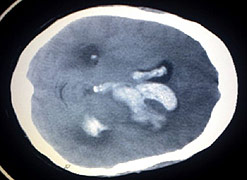

A stroke is what happens when the blood supply to part of the brain is cut off. Without a blood supply, essential nutrients and oxygen can’t get to the brain’s cells and they become damaged or die.

Strokes are caused either by a blockage, when a clot blocks an artery that carries blood to the brain, or when a blood vessel bursts causing a bleed into the brain.

Tests including scans should be carried out quickly to assess the cause of the stroke. Blood-thinning drugs may be given where a clot is involved.